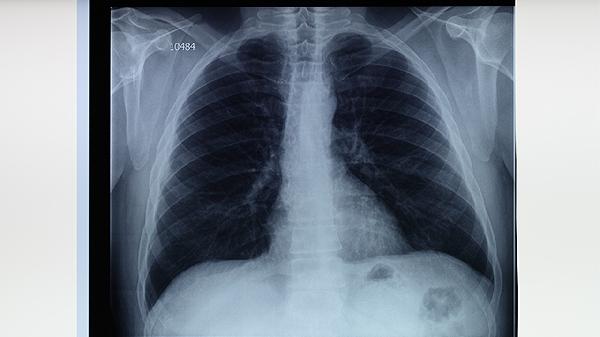

胸部X线可显示肺结核特征性病变,如上叶尖后段或下叶背段的浸润影、空洞形成等。典型表现结合临床症状可初步诊断,但需与肺炎、肺癌等疾病鉴别。该检查对早期粟粒性肺结核检出率较低,孕妇应避免多次照射。CT检查能更清晰显示微小病灶和淋巴结肿大。